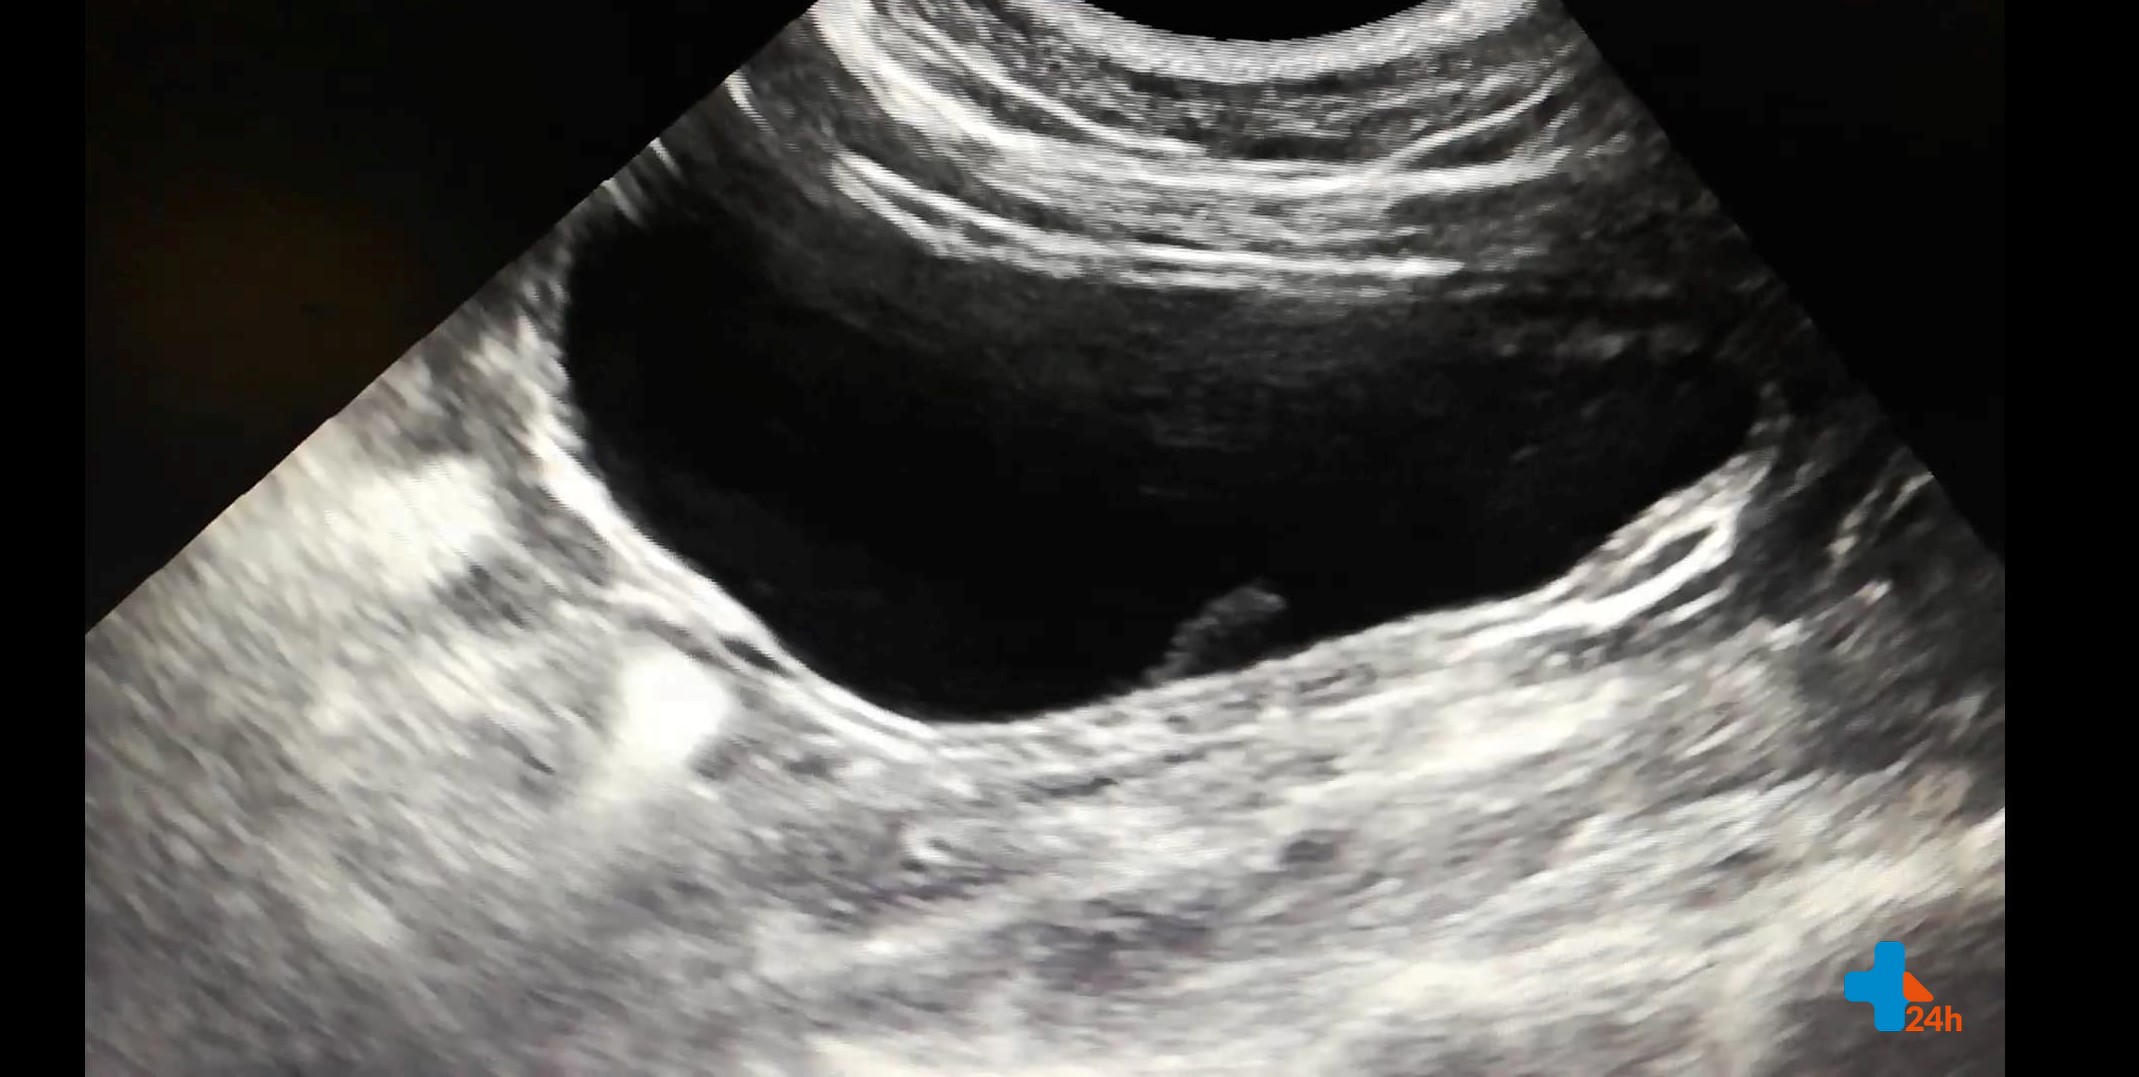

Koty cierpiące na idiopatyczne zapalenie pęcherza moczowego manifestują objawy kliniczne charakterystyczne dla wielu jednostek chorobowych dotyczących dolnych dróg moczowych, dlatego ostateczne rozpoznanie wymaga wnikliwej diagnostyki i wykluczenia istnienia innych chorób urologicznych. Diagnostyka ta obejmuje badanie ogólne moczu, posiew bakteriologiczny, badanie ultrasonograficzne oraz RTG układu moczowego, w pewnych przypadkach uzupełnione o kontrastowanie.